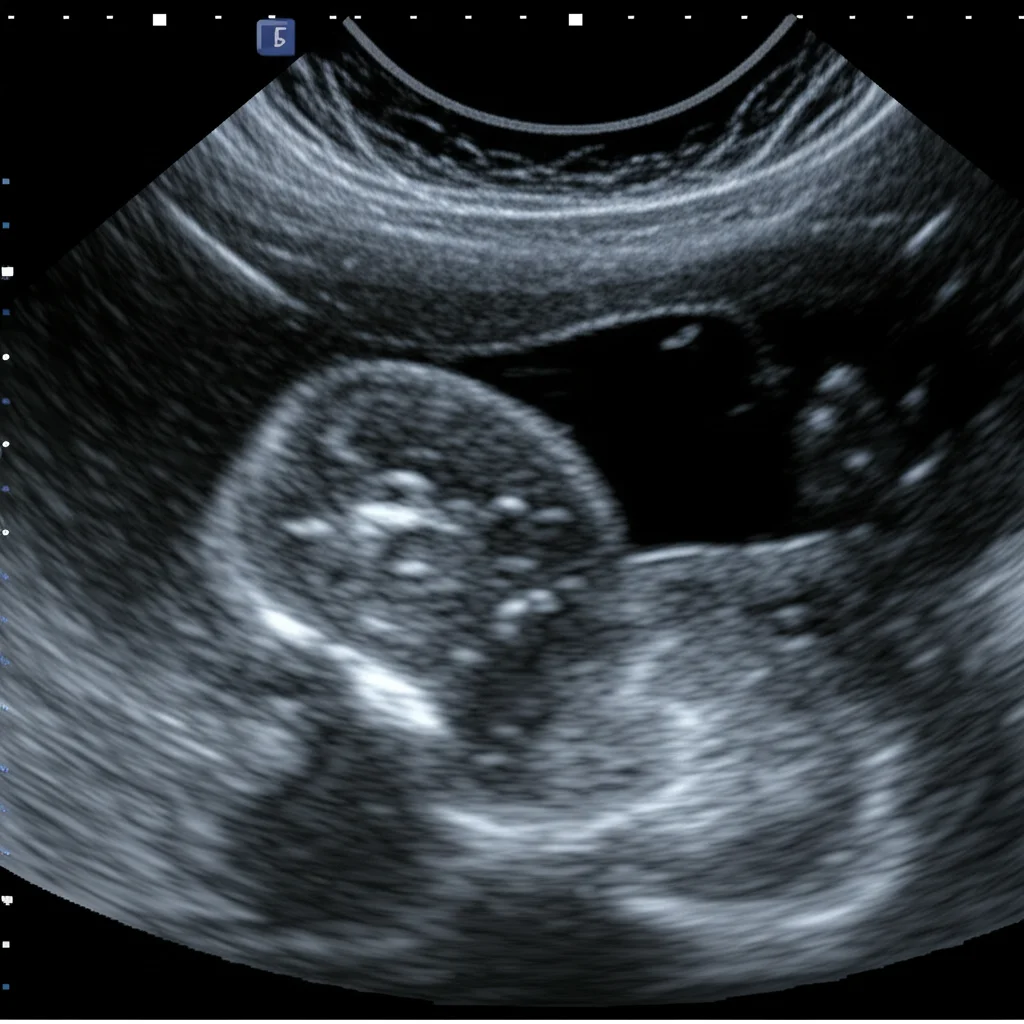

That’s where the **Tiger Model** comes in. Think of it as a special kind of AI that can create images based on text descriptions. We fused clinical insights – all those specific details about how a rare thyroid nodule might appear (its shape, texture, edges, location, etc.) – with powerful image generation technology, specifically diffusion models.

The goal? To produce synthetic ultrasound images that are so realistic and diverse, they can effectively teach AI models to spot these rare subtypes, even when real-world data is limited.

A clever part of the Tiger Model is how it handles the image. It uses separate components (encoders) to focus on the nodule itself (the “foreground”) and the surrounding thyroid tissue and neck structures (the “background”). This allows for really fine-grained control over the generated image details, making them much more convincing and clinically accurate. We used things like segmentation masks to tell the model exactly where the nodule is and edge detection (like a digital sketch) for the background structure.